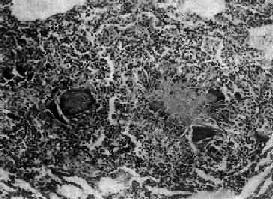

结核结节(tubercle)是在细胞免疫基础上形成的,由类上皮细胞(epithelioid cell)、Langhans巨细胞加上外围局部集聚的淋巴细胞和少量反应性增生的纤维母细胞构成。当有较强的变态反应发生时,结核结节中便出现干酪样坏死。巨噬细胞体积增大逐渐转变为类上皮细胞,呈梭形或多角形,胞浆丰富,染淡伊红色,境界不清。核呈圆或卵圆形,染色质甚少,甚至可呈空泡状,核内可有1~2个核仁。多数类上皮细胞互相融合乃形成Langhans巨细胞,为一种多核巨细胞,体积很大,直径可达300μm,胞浆丰富,核与类上皮细胞核的形态大致相同,核数由十几个到几十个不等,有超过百个者。核排列在胞浆的周围呈花环状、马蹄形或密集在胞体的一端(图18-1)。

图18-1 结核性肉芽肿

结节中央为干酪样坏死,周围绕有类上皮细胞、Langhans巨细胞以及淋巴细胞等